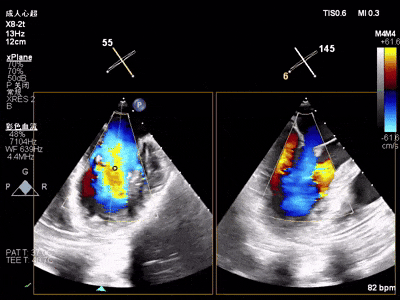

术前心超

功能性MR,P3脱垂,新分型:BAA型

反流主要集中于3区,MR中度,VC:2×4mm

A2:24mm,P2:16mm,AP:38mm,MVA约4.6cm²

术中超声要点

术前术后对比图

术前

术后

术后,出院检查报告显示夹子位置固定,二尖瓣、三尖瓣及主动脉轻微反流,左房增大,左室内径正常上限,EF值正常下限(WMSI 1分)。